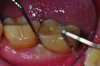

Treatments aimed at controlling inflammation and infection and limiting biologic complications for peri-implant mucositis and peri-implantitis may be identical to those found effective for gingivitis and periodontitis, respectively. Similar to gingivitis, peri-implant mucositis, when detected early, may be successfully treated with effective nonsurgical efforts aimed at elimination of the biofilm from the implant surface10-12 (Figure 5 through Figure 7), through supportive periodontal therapy and mechanical nonsurgical treatment.

However, if the roughened implant surface or threads become exposed, these situations may require implantoplasty—ie, smoothing the outer surface of the dental implant—with burs to facilitate hygiene efforts and reduce plaque accumulation. Perhaps the most important distinction between peri-implant mucositis and peri-implantitis in terms of their clinical implications is that peri-implant mucositis has been shown to respond to nonsurgical treatment,10 whereas peri-implantitis does not.13 Eliminating peri-implantitis may require that a specialist perform advanced technique sensitive surgical procedures that include systemic antibiotics, regeneration,14,15 or combined layered approaches.16

A question often asked is, what are the best instruments to clean around dental implants? There is no one ideal device or method that has been elucidated through a review of the literature.17 The most important point to be made is that implant sites need to be debrided at every recall visit using whatever device might remove the plaque or calculus present while limiting damage to the outer implant surface. In some instances, this may mean that a plastic instrument or one made from titanium may suffice. In other situations, titanium brushes, stainless steel instruments, or subgingival use of air powder abrasion may be necessary.